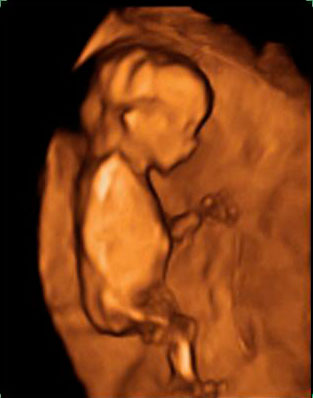

Ecografía Embarazo 4D Semana 12 - PLIEGUE NUCAL